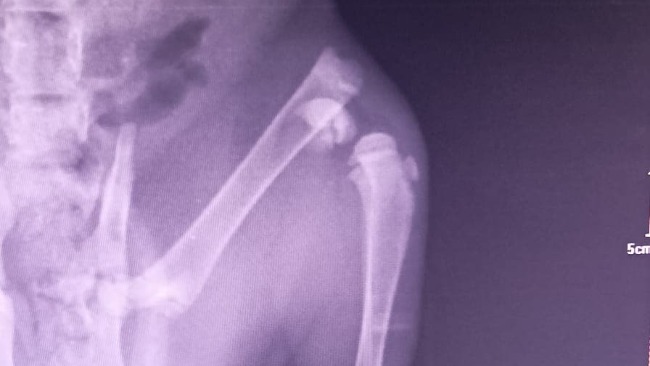

Ma ogromnego krwiaka na lewej tylnej łapce, a RTG wykazało połamanie nasady dalszej kości udowej. To młody kotek, który szybko rośnie. Żeby nie być kaleką, musi przejść pilny zabieg chirurgiczny naprawy łapki!